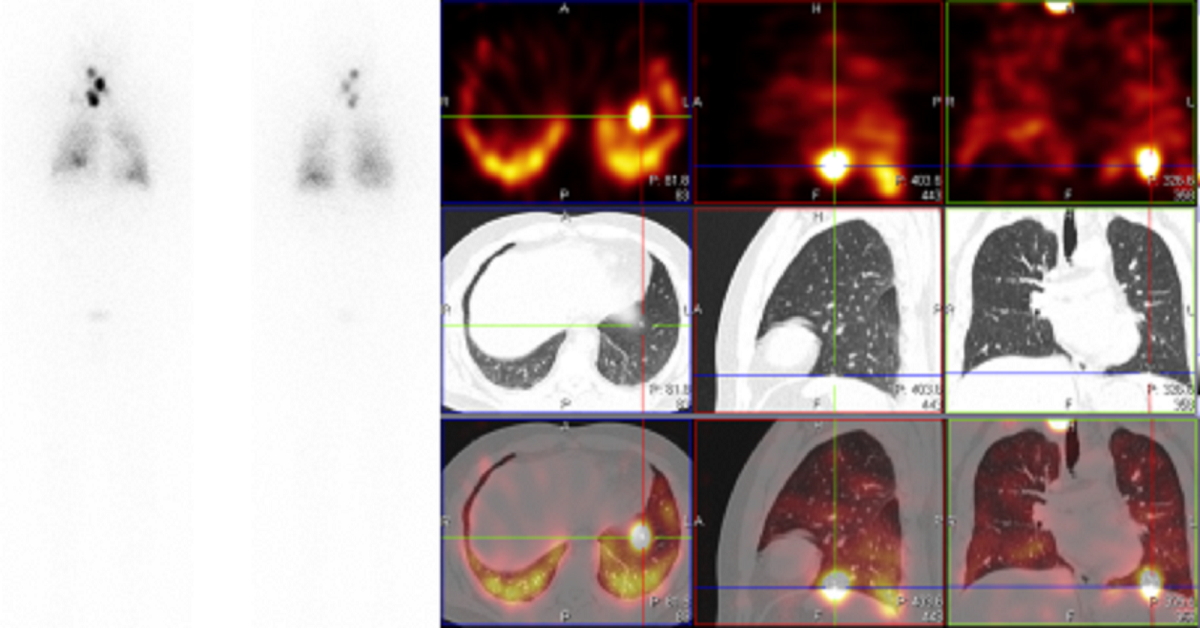

图例2:患者,男,35岁,分化型甲状腺癌术后,行SPECT-CT显像: CT显像左下肺可见粟粒影,余部位未见明显异常

SPECT影像可见左下肺点状异常放射性浓集区及双肺弥漫性异常放射性浓集,考虑双肺摄碘转移灶。